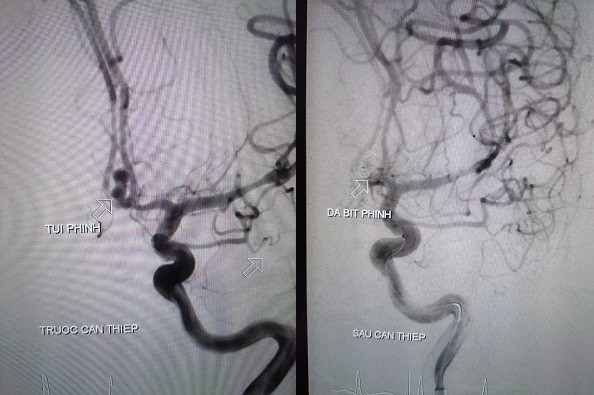

Hình ảnh túi phình mạch não của bệnh nhân trước và sau can thiệp. Ảnh: BVCC

Hình ảnh túi phình mạch não của bệnh nhân trước và sau can thiệp. Ảnh: BVCC

Ngày 14/1, các bác sĩ chỉ định chụp và nút phình động mạch số xóa nền cho bệnh nhân. Ê-kíp do BS.CKI. Trần Công Khánh – Phó Khoa Chẩn đoán hình ảnh, BS. Trịnh Thành Tính – Khoa Ngoại Thần kinh thực hiện.

Kết quả ghi nhận phình động mạch thông trước 4x4mm, các bác sĩ đã chọn lọc vào túi phình, thả 3 vòng xoắn kim loại (coil) bít hoàn toàn túi phình. Kỹ thuật diễn ra thành công sau 1 giờ can thiệp.